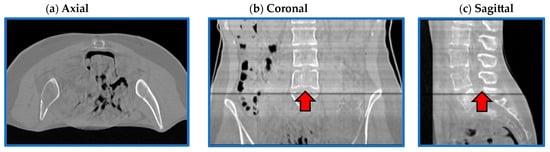

3.4. Qualitative Evaluation